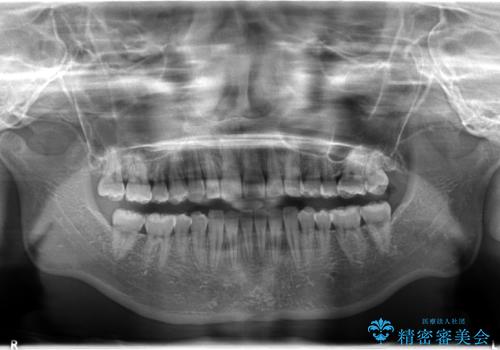

インビザラインで出っ歯を改善する 抜歯をしないinvisalign治療

- 20代女性

- invisalign full

- 1年5ヶ月

- 非抜歯・遠心移動による前突の改善をマウスピースにて計画した。

非抜歯矯正の場合、大きく前歯を下げることはできませんが、奥歯の遠心移動や歯のサイズダウンにより歯軸を立て、見かけ上の出っ歯感をある程度改善することができます。